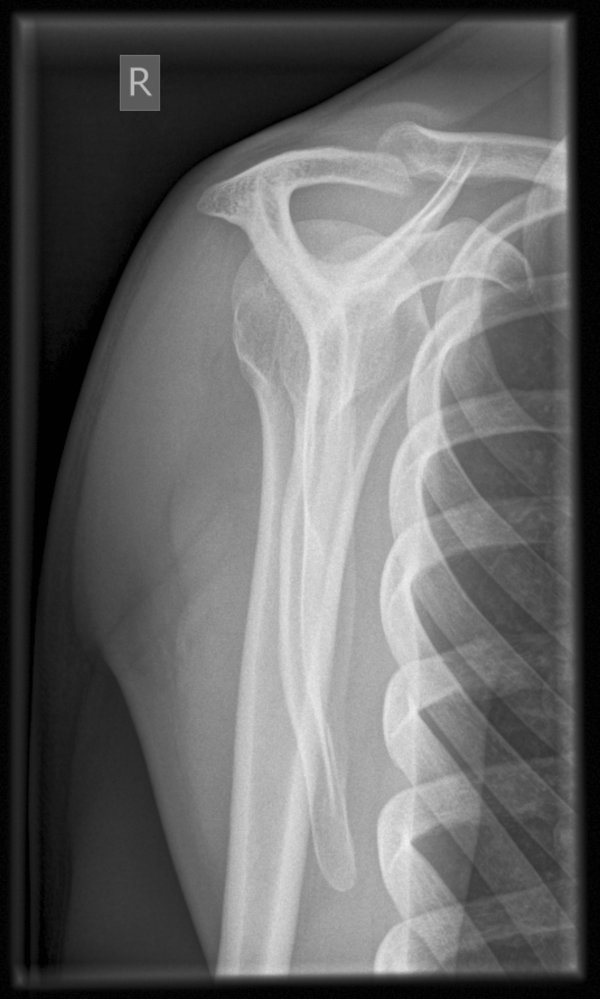

• X-ray (anterior-posterior view, oblique view, axillary view) of the shoulder joint, acromion, and scapula:

• Subluxation of the AC joint space

• Widening of the CC space

• Displacement of the clavicle

• Accompanying injuries (e.g., clavicle fracture)